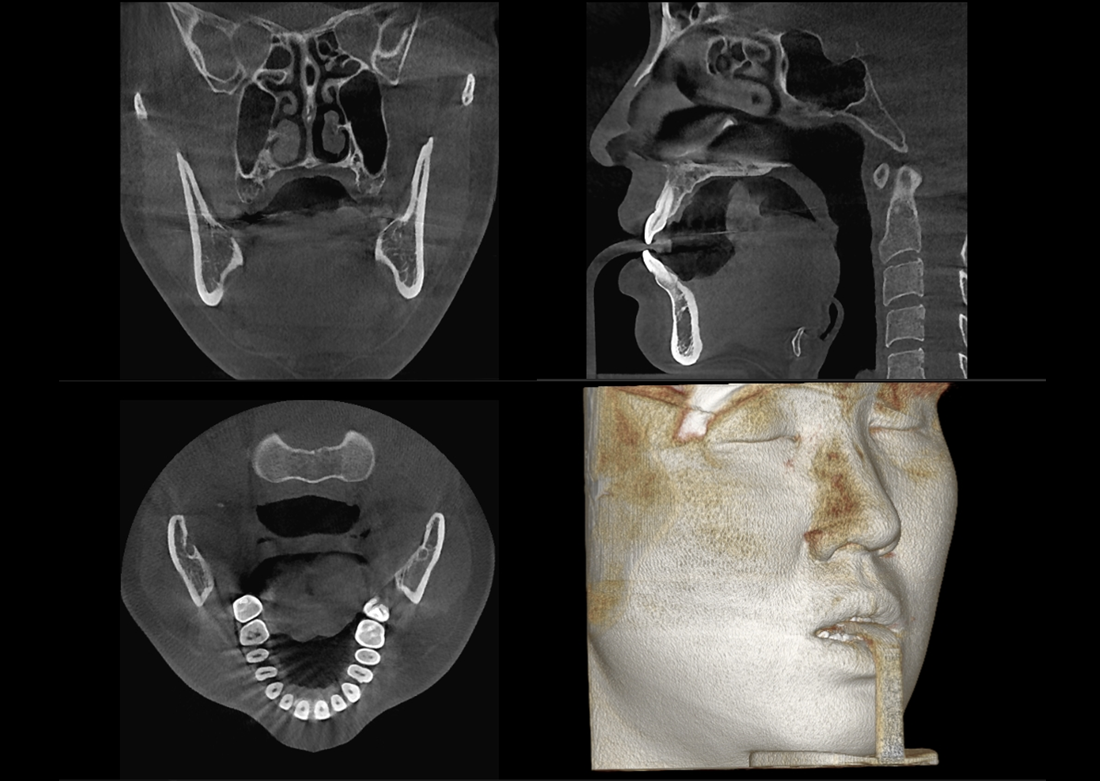

The Papaya 3D Premium/Ultra is the newest generation in a long line of Genoray products designed to produce accurate diagnostic images with wider treatment applications including implants, endo, ortho, airway, TMJ, and orthognathic surgeries. Optimized acquisition PC/Monitor/Accessories, model scan/STL converter, and perpetually licensed software suites included.

Both the 3D Premium and 3D Ultra models are available with an optional patient stool (smart memory), and Scan or One-Shot Cephalometric attachments.

- Papaya 3D Ultra CBCT: Min 4x5 to Max 23x24* FOV

*Papaya 3D Ultra comes supplied with free Invivo software, enabling CT extrapolated cephalometric images.